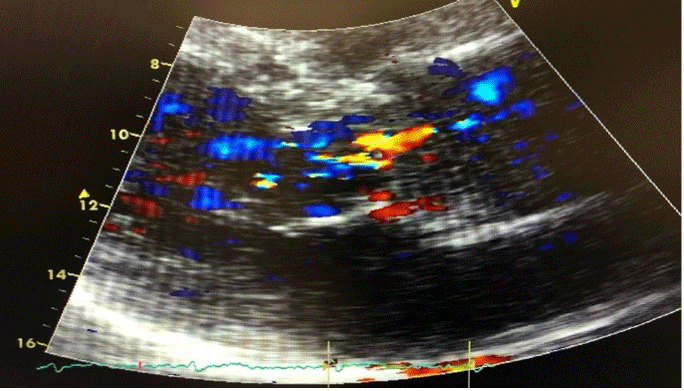

约25%被诊断患有冠状病毒病19 (COVID-19)的患者出现心血管并发症,导致40%的相关死亡。在此,我们讨论一位69岁男性,有充血性心力衰竭病史,并在纽约心脏协会(NYHA) II级保留射血分数,表现为新的呼吸困难,咳嗽和阵发性夜间呼吸困难。他随后被诊断为COVID-19肺炎,虽然他最初康复,但后来症状恶化,进展为NYHA IV级。随访超声心动图显示射血分数下降至40%,主动脉严重不全。他接受了主动脉瓣置换术,缓解了症状。该病例突出了COVID-19导致瓣膜疾病快速进展的可能性。

About 25% of patients diagnosed with coronavirus disease 19 (COVID-19) experience cardiovascular complications, contributing to 40% of related deaths. Here we discuss a 69-year-old male with a history of congestive heart failure and preserved ejection fraction at New York Heart Association (NYHA) class II who presented with new dyspnea, cough, and paroxysmal nocturnal dyspnea. He was subsequently diagnosed with COVID-19 pneumonia, and while he initially recovered, he later showed worsening symptoms with progression to NYHA class IV. Follow-up echocardiogram revealed a decline in ejection fraction to 40% and severe aortic insufficiency. He underwent surgical aortic valve replacement, resolving his symptoms. This case highlights COVID-19's potential to cause rapid progression of valvular disease.